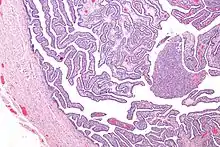

Definitive criteria include histopathologic evidence of endometritis, thickened filled Fallopian tubes, or laparoscopic findings. Gram stain/smear becomes definitive in the identification of rare, atypical and possibly more serious organisms.[24] Two thirds of patients with laparoscopic evidence of previous PID were not aware they had PID, but even asymptomatic PID can cause serious harm.